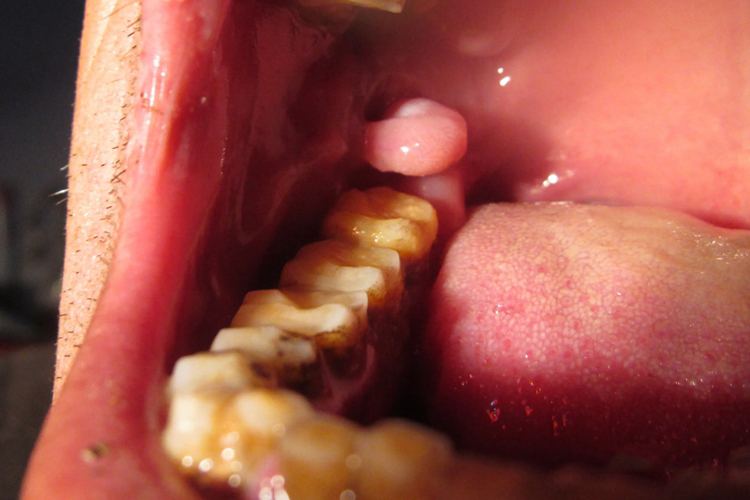

口腔内右侧长了个肉坨可能是由多种原因引起的,包括牙周炎、黏液腺囊肿、口腔息肉等,可以在医生指导下采取药物治疗、手术切除等措施。

5、黏液腺囊肿:黏液腺囊肿是一种常见的口腔良性肿瘤,通常由于唾液腺导管受损或堵塞导致唾液无法正常排出,从而形成囊肿。多数约黄豆大小,呈半透明的无痛小疱,破裂后可流出黏液,肿胀消退,但不久后可复发。若囊肿持续存在或增大,建议就医进行手术分离并去除囊肿。

6、口腔息肉:息肉是一种良性肿瘤,由口腔黏膜组织过度生长形成。口腔内出现肉坨,可能伴有脓液或疼痛。小的息肉可以通过激光治疗去除,若息肉较大或影响到正常咀嚼,建议尽快手术切除。

7、牙龈瘤:牙龈瘤是一种生长在牙龈组织上的良性肿瘤。可能导致牙龈肿胀,可能由于慢性炎症、局部刺激或其他原因引起。就医进行详细检查,根据医生建议选择适合的治疗方案,可能包括手术切除等。